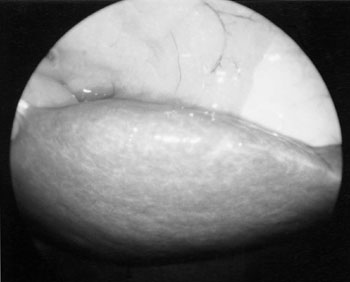

C型慢性肝炎の腹腔写真。肝臓の表面凹凸は軽度で赤みもなく落ちついた肝炎。